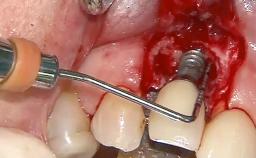

Peri-Implant Tissue Health

Maintenance of healthy peri-implant soft tissue as well as supporting peri-implant bone is an essential part of long-term success of implant therapy. An accurate maintenance protocol of peri-implant tissue health may prevent biological complications such as peri-implantitis. After the delivery of the prosthesis, patients should be followed up and clinical and radiological examinations should be performed on a regular basis to detect any etiological factors that may lead to such complications. This topic discusses properties of healthy and pathological conditions of peri-implant tissue, clinical and radiological examination methods of peri-implant tissue, as well as protocols for maintaining peri-implant tissue health.